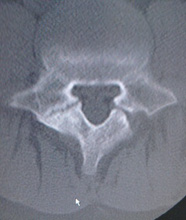

4.脊柱管狭窄症

加齢、労働、あるいは背骨の病気による影響で変形した椎間板と、背骨や椎間関節から突出した骨などにより、神経が圧迫されます。

脊柱管は背骨、椎間板、関節、黄色靱帯などで囲まれた脊髄の神経が通るトンネルです。歳をとると背骨が変形したり、椎間板が膨らんだり、黄色靱帯が厚くなって神経の通る脊柱管が狭くなって(狭窄)、それによって神経が圧迫され、神経の血流が低下して脊柱管狭窄症が発症します。

脊柱管狭窄症は長い距離を続けて歩くことができません。最も特徴的な症状は、歩行と休息を繰り返す間歇性跛行です。

安静にしている時にはほとんど症状はありませんが、背筋を伸ばして立っていたり歩いたりすると、ふとももや膝から下にしびれや痛みがでて歩きづらくなります。しかし、すこし前かがみになったり、腰かけたりするとしびれや痛みは軽減されます。

症状が進行すると、下肢の力が落ちたり、肛門周囲のほてりや尿の出が悪くなったり、逆に尿が漏れることもあります。